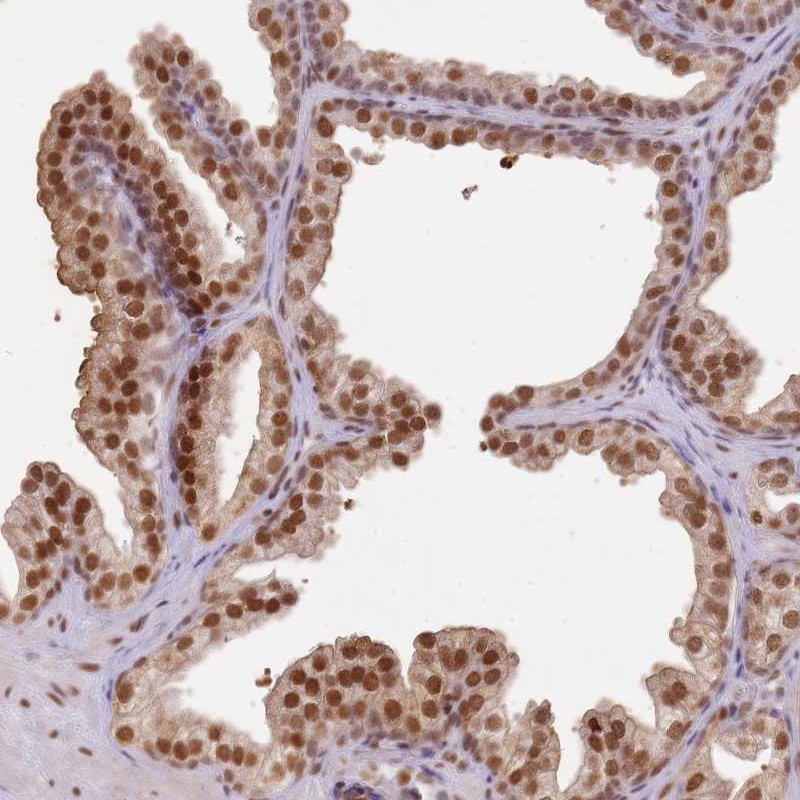

Immunohistochemical staining of human prostate shows distinct nuclear positivity in glandular cells.